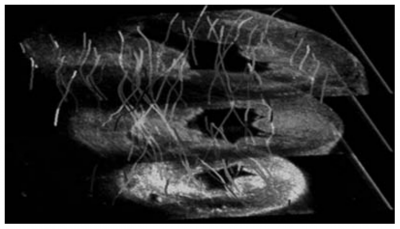

This work reports on the development and evaluation of the PET component of a PET/CT system for small-animal in-vivo imaging. The PET and CT subsystems are assembled in a rotary gantry in such a way that the center of rotation for both imaging modalities is mechanically aligned. The PET scanner configuration is based on 2 detector modules, each of which consist of 2 flat-panel type PS-PMTs (Hamamatsu, H8500) and 2 (30 × 30 elements) LYSO arrays.

In this work we characterized a recently developed gamma imager for small animal SPECT applications. The Hamamatsu C9177 is a mini-gamma camera that integrates the detector and all the electronics, including the acquisition system, in a compact and portable housing. The detector is based on a high resolution parallel hole collimator, a CsI(NaI) crystal array and a PS-PMT (flat panel type). |